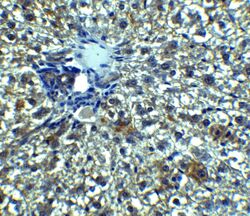

Supportive validation

- Submitted by

- Invitrogen Antibodies (provider)

- Main image

- Experimental details

- Immunohistochemistry of Betatrophin in rat liver tissue with betatrophin Polyclonal Antibody (Product # PA5-38043) at 5 µg/mL.